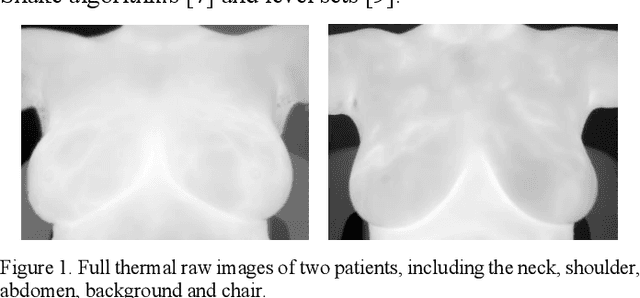

Abstract:Breast cancer is the second leading cause of death for women in the U.S. Early detection of breast cancer is key to higher survival rates of breast cancer patients. We are investigating infrared (IR) thermography as a noninvasive adjunct to mammography for breast cancer screening. IR imaging is radiation-free, pain-free, and non-contact. Automatic segmentation of the breast area from the acquired full-size breast IR images will help limit the area for tumor search, as well as reduce the time and effort costs of manual segmentation. Autoencoder-like convolutional and deconvolutional neural networks (C-DCNN) had been applied to automatically segment the breast area in IR images in previous studies. In this study, we applied a state-of-the-art deep-learning segmentation model, MultiResUnet, which consists of an encoder part to capture features and a decoder part for precise localization. It was used to segment the breast area by using a set of breast IR images, collected in our pilot study by imaging breast cancer patients and normal volunteers with a thermal infrared camera (N2 Imager). The database we used has 450 images, acquired from 14 patients and 16 volunteers. We used a thresholding method to remove interference in the raw images and remapped them from the original 16-bit to 8-bit, and then cropped and segmented the 8-bit images manually. Experiments using leave-one-out cross-validation (LOOCV) and comparison with the ground-truth images by using Tanimoto similarity show that the average accuracy of MultiResUnet is 91.47%, which is about 2% higher than that of the autoencoder. MultiResUnet offers a better approach to segment breast IR images than our previous model.